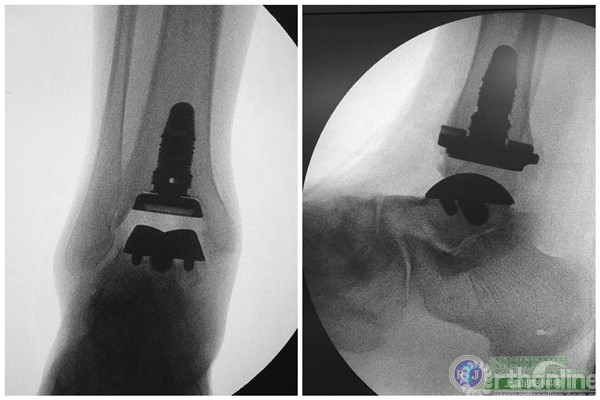

为了改变这种现状,造福广大的踝关节炎患者,瑞金医院足踝外科率先在国内开展第三代全踝关节假体置换手术,使用美国Wright公司的第三代全踝人工关节系统——INBONE II为这名患者解决病痛。

上海瑞金医院骨科足踝外科团队于2015年10月28日上午成功对该患者实施了第三代全踝关节假体(INBONE® II. Wright.)置换手术,手术过程非常顺利。手术中首先清理踝关节内外侧炎性组织及骨赘,将患足置于专门的定制支架中,在透视下反复调整足踝及导针位置,力求最高精确度。在截骨导板的定位下进行踝关节胫骨及距骨的截骨,试样假体大小,置入合适匹配的踝关节假体及垫片完成全踝关节假体的置换,全程手术时间90分钟。完成的全踝关节假体置换位置精确,假体设计稳定牢固,踝关节内外侧软组织平衡,达到了预期的效果。术后患者恢复良好,手术取得圆满成功。患者在休养五周左右以后可以下地行走,去除踝关节炎疼痛畸形的同时能够保留踝关节的活动度,为生活和工作提供极大便利。

国内首例INBONE全踝关节假体置换手术的成功完成开启了中国骨科手术治疗终末期踝关节炎的新篇章,这为千千万万饱受踝关节炎困扰的患者带来了福音。